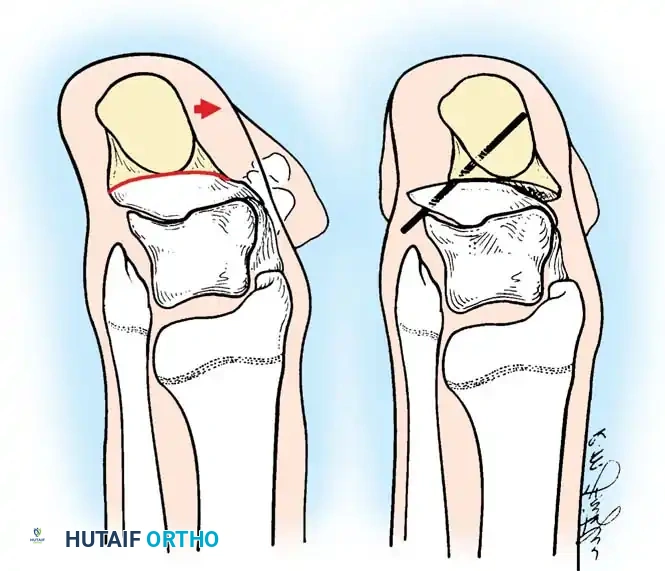

## فهم طبيعة المشكلة وكيفية حدوثها لفهم كيفية حدوث تشوهات القدم في الشلل الدماغي، يجب أن ننظر إلى العلاقة المعقدة بين الأعصاب والعضلات والعظام. في الحالة الطبيعية، تعمل العضلات في أزواج متوازنة (عضلات تشد وأخرى ترخي) لتوجيه حركة المفصل. ولكن في حالة الشلل الدماغي، ترسل الإشارات العصبية غير المنتظمة أوامر مستمرة لبعض العضلات بالانقباض (التشنج)، مما يخلق قوى غير طبيعية وغير متكافئة على عظام ومفاصل القدم. النوع الأكثر شيوعاً من هذه التشوهات هو "القدم الخيلية" أو المشي على أطراف الأصابع، حيث تكون القدم مشدودة لأسفل. وتحدث تشوهات أخرى مثل انحراف القدم للداخل أو انحراف القدم للخارج بنسب متقاربة، وذلك يعتمد بشكل كبير على التوزيع التشريحي للإصابة العصبية لدى الطفل. وقد أثبتت الدراسات الكبرى أن وجود تشوه في القدم، خاصة إذا كان في كلتا القدمين، يؤثر بشكل سلبي وكبير على قدرة الطفل على المشي ويزيد من المجهود البدني المطلوب للحركة مقارنة بالأطفال الذين يعانون من إصابة في قدم واحدة.  ## أسباب وعوامل تطور تشوهات القدم من المهم جداً للآباء أن يدركوا أن تشوهات القدم في الشلل الدماغي نادراً ما تكون ثابتة؛ بل هي تتطور وتتغير ديناميكياً بمرور الوقت، وتحديداً خلال فترات النمو السريع لهيكل الطفل العظمي. تكمن المشكلة الأساسية في أن العظام تنمو بمعدل طبيعي، بينما العضلات المتشنجة والمشدودة (مثل عضلة الساق الخلفية) لا تنمو بنفس السرعة وتفتقر إلى المرونة اللازمة لمواكبة نمو العظام. هذا التفاوت يؤدي إلى قصر نسبي في العضلة والوتر، مما يسحب القدم إلى وضعيات غير طبيعية. على سبيل المثال، قد يبدأ الطفل الصغير بتشوه مرن في القدم، ولكن مع استمرار التشنج العضلي وقوى الشد غير الطبيعية أثناء المشي، قد يتحول هذا التشوه المرن بمرور الوقت إلى تشوه عظمي صلب وتيبس كامل في المفصل. بالإضافة إلى ذلك، فإن تشنج العضلات الدقيقة داخل القدم يمكن أن يؤدي إلى تشوهات ثانوية في الأصابع ومقدمة القدم، مثل انحراف إصبع القدم الأكبر أو التصاق الأصابع. ## الأعراض والعلامات التحذيرية التشوه الأبرز والأكثر شيوعاً هو "القدم الخيلية"، والذي يصيب ما يصل إلى 70% من الأطفال المصابين. وهناك علامات يجب على الآباء الانتباه لها: * المشي المستمر على أطراف الأصابع وعدم القدرة على ملامسة الكعب للأرض. * رجوع الركبة للخلف بشدة أثناء الوقوف أو المشي للتعويض عن قصر وتر أخيل. * صعوبة بالغة في إدخال قدم الطفل في الحذاء العادي. * تآكل الحذاء بشكل غير متساوٍ من جهة معينة. * ألم في القدم أو الساق بعد المشي لمسافات قصيرة. * ظهور تقرحات جلدية في مناطق الضغط غير الطبيعي، خاصة لدى الأطفال الذين يستخدمون الكراسي المتحركة. ## التقييم الطبي والتشخيص يبدأ التقييم الطبي الدقيق بزيارة طبيب جراحة عظام الأطفال المتخصص. سيقوم الطبيب بإجراء فحص سريري شامل لتقييم: * مدى التشنج العضلي في الساق والقدم. * الفرق بين التشوه المرن الذي يمكن تصحيحه باليد، والتشوه الصلب (الثابت). * تحليل نمط مشي الطفل. * إجراء اختبارات خاصة مثل اختبار سيلفرسكيولد لتحديد ما إذا كان الشد ناتجاً عن عضلة الساق العلوية فقط أم يمتد ليشمل وتر أخيل بالكامل. ## الخيارات العلاجية غير الجراحية يعتبر العلاج التحفظي (غير الجراحي) هو خط الدفاع الأول، والهدف الأساسي منه هو الحفاظ على مرونة المفاصل، وتحسين وظيفة القدم، وتأخير الحاجة للتدخل الجراحي قدر الإمكان حتى يكبر الطفل، مما يقلل من احتمالية عودة التشوه. تشمل الخيارات غير الجراحية ما يلي: ### العلاج الطبيعي المكثف يركز العلاج الطبيعي على تمارين الإطالة السلبية للعضلات المتشنجة. وقد أثبتت الأبحاث أن العضلة تحتاج إلى فترات طويلة من الإطالة اليومية لمنع حدوث قصر دائم فيها، وهو ما يتطلب التزاماً كبيراً من الأسرة. ### استخدام الجبائر والأجهزة التعويضية تعتبر الجبائر البلاستيكية الداعمة للكاحل والقدم من أهم أدوات العلاج. وتستخدم الجبائر الليلية الصلبة بشكل خاص للحفاظ على القدم في وضع معتدل ولمواجهة التشنجات التي تزيد أثناء النوم. ### الحقن والجبس المتسلسل يُعد حقن البوتكس في العضلات المتشنجة إجراءً فعالاً لإرخاء العضلة مؤقتاً. وغالباً ما يُتبع الحقن بوضع سلسلة من قوالب الجبس التي يتم تغييرها كل أسبوعين إلى ثلاثة أسابيع لإطالة العضلة تدريجياً وتحسين المدى الحركي للمفصل.  | نوع العلاج التحفظي | الهدف الرئيسي | ملاحظات هامة | | :--- | :--- | :--- | | العلاج الطبيعي | الحفاظ على مرونة العضلات والمفاصل | يحتاج إلى استمرارية والتزام يومي | | الجبائر التقويمية | منع تفاقم التشوه وتثبيت القدم | ضرورية جداً أثناء فترات النوم | | حقن البوتكس | إرخاء العضلات المتشنجة مؤقتاً | تأثيره يستمر لعدة أشهر ويساعد في تأخير الجراحة | | الجبس المتسلسل | إطالة الأوتار تدريجياً | يستخدم غالباً بالتزامن مع حقن البوتكس | ## دواعي التدخل الجراحي لتشوهات القدم يصبح التدخل الجراحي ضرورياً عندما تفشل الطرق التحفظية في السيطرة على التشوه، أو عندما يصبح التشوه ثابتاً ويعيق حياة الطفل. تختلف دواعي الجراحة بناءً على قدرة الطفل على المشي: **للأطفال القادرين على المشي:** يتم اللجوء للجراحة عند عدم قدرة الطفل على وضع كاحله في زاوية قائمة أثناء المشي مع فرد الركبة، مما يؤدي إلى المشي على أطراف الأصابع، أو التواء الركبة للخلف، أو رفع الكعب مبكراً أثناء المشي. **للأطفال غير القادرين على المشي:** تُجرى الجراحة لتخفيف التقلصات الشديدة التي تمنع ارتداء الأحذية، أو تعيق برامج الوقوف المدعوم، أو تتسبب في تقرحات جلدية وصعوبات في النظافة الشخصية. > **تحذير جراحي بالغ الأهمية خطر الإطالة المفرطة** > يجب على الجراح توخي الحذر الشديد لتجنب الإطالة المفرطة لوتر أخيل أو عضلة الساق، خاصة لدى الأطفال الذين يمشون. الإطالة الزائدة تدمر القوة الدافعة للقدم وتؤدي إلى تطور ما يُعرف بـ "مشي القرفصاء". هذا النمط من المشي كارثي من الناحية الميكانيكية، حيث يؤدي إلى إرهاق سريع لعضلات الفخذ الأمامية وفقدان القدرة على المشي المستقل.  ## عمليات تطويل وتر أخيل نظراً لاختلاف حالات الشلل الدماغي، توجد تقنيات جراحية متعددة لتصحيح تشوه القدم الخيلية. تعتمد نسبة نجاح العملية وعدم عودة التشوه بشكل كبير على عمر الطفل وقت الجراحة ونوع الشلل الدماغي. تشير الدراسات إلى أن إجراء الجراحة بعد سن السادسة يقلل بشكل كبير من احتمالية عودة التشوه مقارنة بإجرائها في سن مبكرة جداً. يمكن إطالة مجمع عضلة الساق ووتر أخيل في مستويين رئيسيين: إما عند اتصال العضلة بالوتر، أو في وتر أخيل نفسه. ### التطويل المفتوح لوتر أخيل تُستخدم هذه التقنية (وتعرف بتعديل وايت) وتعتمد على الانزلاق الطبيعي لألياف وتر أخيل التي تلتف حول نفسها بطبيعتها التشريحية.  **خطوات العملية الجراحية:** * يتم عمل شق جراحي طولي خلف الكاحل للوصول إلى الوتر. * يقوم الجراح بعمل قطع جزئي في الجزء السفلي من الوتر، وقطع جزئي آخر في الجزء العلوي في اتجاه معاكس. * عندما يتم دفع القدم بلطف إلى الأعلى (نحو الساق)، تنزلق ألياف الوتر المقطوعة فوق بعضها البعض، مما يؤدي إلى زيادة طول الوتر للمستوى المطلوب لتصحيح التشوه. * تتميز هذه الطريقة بالحفاظ على الغلاف المحيط بالوتر لمنع الالتصاقات.   بعد العملية، يتم وضع قدم الطفل في جبس قصير يمتد تحت الركبة لمدة 4 أسابيع، ويُسمح للطفل بالمشي عليه. بعد إزالة الجبس، يتم استخدام جبيرة بلاستيكية مخصصة للحفاظ على النتيجة. ### التطويل على شكل حرف زد توفر هذه التقنية تحكماً دقيقاً للغاية في مقدار الإطالة المطلوبة، مما يجعلها الخيار الأمثل للتقلصات الشديدة والصلبة.  **كيف تتم العملية؟** * يتم شق الوتر طولياً في المنتصف، ثم يتم قطع نصف الوتر من الأسفل والنصف الآخر من الأعلى، مما يشكل حرف Z. * يتم سحب الأطراف لزيادة الطول بدقة متناهية، ثم يتم خياطة الأطراف معاً باستخدام خيوط جراحية قوية. * يتم ضبط درجة شد الوتر بناءً على شدة التشنج العضلي لدى الطفل لضمان أفضل نتيجة وظيفية.      يتطلب هذا الإجراء وضع جبس لمدة 6 أسابيع، يليه استخدام الجبائر الداعمة بشكل مستمر لتجنب سقوط القدم. ### التطويل عن طريق الجلد تعتبر هذه التقنية إجراءً سريعاً وبسيطاً يتم إجراؤه غالباً كجراحة يوم واحد، وتتميز بآثار ندبات شبه معدومة ونتائج ممتازة.  **تفاصيل الإجراء:** * يقوم الجراح بعمل ثلاثة شقوق صغيرة جداً (ثقوب) في الجلد فوق وتر أخيل باستخدام شفرة دقيقة. * يتم قطع نصف الوتر من خلال هذه الثقوب في مستويات مختلفة (أسفل، وسط، أعلى). * عند دفع القدم للأعلى، تنزلق الألياف وتستطيل العضلة، وغالباً ما يُسمع صوت "طقطقة" بسيطة تدل على تحرر الوتر ووصوله للطول المطلوب. * لا يتطلب هذا الإجراء خياطة جراحية، بل يتم وضع أشرطة لاصقة معقمة ثم الجبس.   ## عمليات إطالة عضلة الساق الخلفية عندما يظهر الفحص الطبي أن المشكلة تكمن فقط في الجزء العلوي من عضلة الساق (عضلة السمانة)، أو عندما يريد الجراح تقليل خطر الإطالة المفرطة لدى طفل قادر على المشي، يتم اللجوء إلى إطالة الغشاء العضلي لعضلة الساق بدلاً من قطع وتر أخيل السفلي. هناك عدة طرق جراحية تاريخية وحديثة لهذا الإجراء (مثل تقنية ستراير، فولبيوس، وبيكر)، وتعتمد جميعها على فصل الغشاء الليفي للعضلة في منطقة اتصالها بالوتر، مما يسمح للعضلة بالتمدد والاستطالة مع الحفاظ على قوة الدفع الأساسية للقدم.   أثبتت الدراسات أن هذه التقنية تعطي نتائج ممتازة ونسبة عودة للتشوه لا تتجاوز 4% عند اختيار المريض المناسب. > **معلومة طبية هامة** > في الماضي، كان بعض الجراحين يقومون بقطع جزء من الأعصاب المغذية للعضلة لتقليل التشنج. هذا الإجراء لم يعد مستخدماً في الطب الحديث، حيث يتم السيطرة على التشنج الآن بطرق أفضل مثل حقن البوتكس أو عمليات إطالة الأوتار.   بعد هذه الجراحة، يتم وضع جبس لمدة 4 أسابيع، ويُنصح بشدة بالبدء في العلاج الطبيعي المكثف بعد فك الجبس للحفاظ على مرونة المفصل، مع استخدام الجبائر الليلية لمدة لا تقل عن 6 أشهر.   ## علاج اعوجاج القدم للداخل أو الخارج بينما يعتبر المشي على أطراف الأصابع هو التشوه الأكثر شيوعاً، فإنه غالباً ما يكون مصحوباً بانحراف القدم للداخل أو الخارج. اتجاه الانحراف يعتمد على نوع الشلل الدماغي وقوة العضلات المتشنجة التي تسحب القدم في اتجاهها. في حالات الشلل النصفي، غالباً ما تنحرف القدم للداخل. أما في حالات الشلل المزدوج أو الرباعي، فغالباً ما تنحرف القدم للخارج وتصبح مسطحة. **المبادئ الجراحية لتصحيح الاعوجاج:** انحراف القدم للداخل يعتبر أكثر إعاقة للطفل لأنه يجعله يمشي على الحافة الخارجية للقدم، مما يسبب عدم استقرار وصعوبة في استخدام الجبائر. لذلك يتم التدخل الجراحي مبكراً. يتطلب تصحيح هذه التشوهات التعامل مع شقين: 1. **التشوه الديناميكي العضلي:** يتم علاجه عن طريق نقل الأوتار (مثل نقل نصف وتر العضلة الأمامية للساق) لإعادة التوازن لقوى الشد في القدم. 2. **التشوه العظمي الثابت:** إذا كان التشوه قد أثر على شكل العظام، يتطلب الأمر تدخلاً في العظام نفسها، مثل إجراء قص عظمي في عظمة الكعب لتعديل مسارها وإعادة القدم لوضعها المسطح الطبيعي الذي يسمح بارتداء الأحذية والجبائر.    ## مرحلة التعافي وما بعد الجراحة تعتبر فترة ما بعد الجراحة بنفس أهمية الجراحة ذاتها لضمان نجاح العلاج. * **الجبس:** يبقى الطفل في الجبس لفترة تتراوح بين 4 إلى 6 أسابيع حسب نوع الإجراء. * **المشي:** في كثير من الحالات، يُسمح للطفل بالمشي على الجبس بمجرد زوال الألم الأولي (عادة بعد 5 إلى 10 أيام). * **الجبائر:** بعد إزالة الجبس، يكون استخدام الجبائر البلاستيكية (AFO) إلزامياً، إما طوال اليوم أو أثناء الليل فقط، وذلك حسب حالة الطفل وقوة عضلاته. * **العلاج الطبيعي:** يبدأ برنامج مكثف للعلاج الطبيعي لتقوية العضلات الضعيفة وتدريب الطفل على نمط المشي الجديد والصحيح. ## الأسئلة الشائعة حول تشوهات القدم في الشلل الدماغي ### متى يجب التدخل الجراحي لعلاج تشوهات القدم؟ يُنصح بالتدخل الجراحي عندما تفشل العلاجات التحفظية (مثل الجبائر والعلاج الطبيعي) في تحسين المشي، أو عندما يصبح التشوه ثابتاً ويسبب ألماً أو يمنع الطفل من ارتداء الأحذية والمشي بشكل متوازن. ### هل يمكن أن تعود التشوهات بعد إجراء العملية الجراحية؟ نعم، هناك احتمالية لعودة التشوه، وتعتمد النسبة على عمر الطفل وقت الجراحة وشدة التشنج. إجراء الجراحة بعد سن السادسة يقلل بشكل كبير من احتمالية الانتكاس، بالإضافة إلى الالتزام بارتداء الجبائر بعد العملية. ### ما هي مدة بقاء الجبس بعد عملية تطويل الأوتار؟ عادة ما يستمر وضع الجبس لمدة تتراوح بين 4 إلى 6 أسابيع، وذلك يعتمد على نوع التقنية الجراحية المستخدمة وما إذا كانت هناك إجراءات إضافية على العظام. ### هل يمكن علاج المشي على أطراف الأصابع بدون جراحة؟ في المراحل المبكرة وعندما يكون التشوه مرناً، يمكن السيطرة عليه باستخدام العلاج الطبيعي المكثف، الجبائر الليلية، وحقن البوتكس. ولكن إذا أصبح الوتر قصيراً بشكل دائم، تصبح الجراحة ضرورية. ### ما هو مشي القرفصاء ولماذا يحذر منه الأطباء؟ مشي القرفصاء يحدث عندما يتم إطالة وتر أخيل بشكل مبالغ فيه أثناء الجراحة، مما يفقد القدم قوة الدفع، فيضطر الطفل لثني ركبتيه بشكل مستمر أثناء المشي. هذا النمط مرهق جداً وقد يفقد الطفل القدرة على المشي المستقل. ### هل حقن البوتكس تغني عن العملية الجراحية؟ البوتكس علاج مؤقت يعمل على إرخاء العضلة المتشنجة لعدة أشهر، ويساعد في تأخير الحاجة للجراحة حتى يصل الطفل لعمر مناسب، لكنه لا يعالج القصر العضلي الثابت ولا يغني عن الجراحة في الحالات المتقدمة. ### متى يستطيع الطفل المشي بعد العملية؟ في معظم عمليات إطالة الأوتار، يُسمح للطفل بالبدء في المشي التدريجي وهو يرتدي الجبس بمج ---